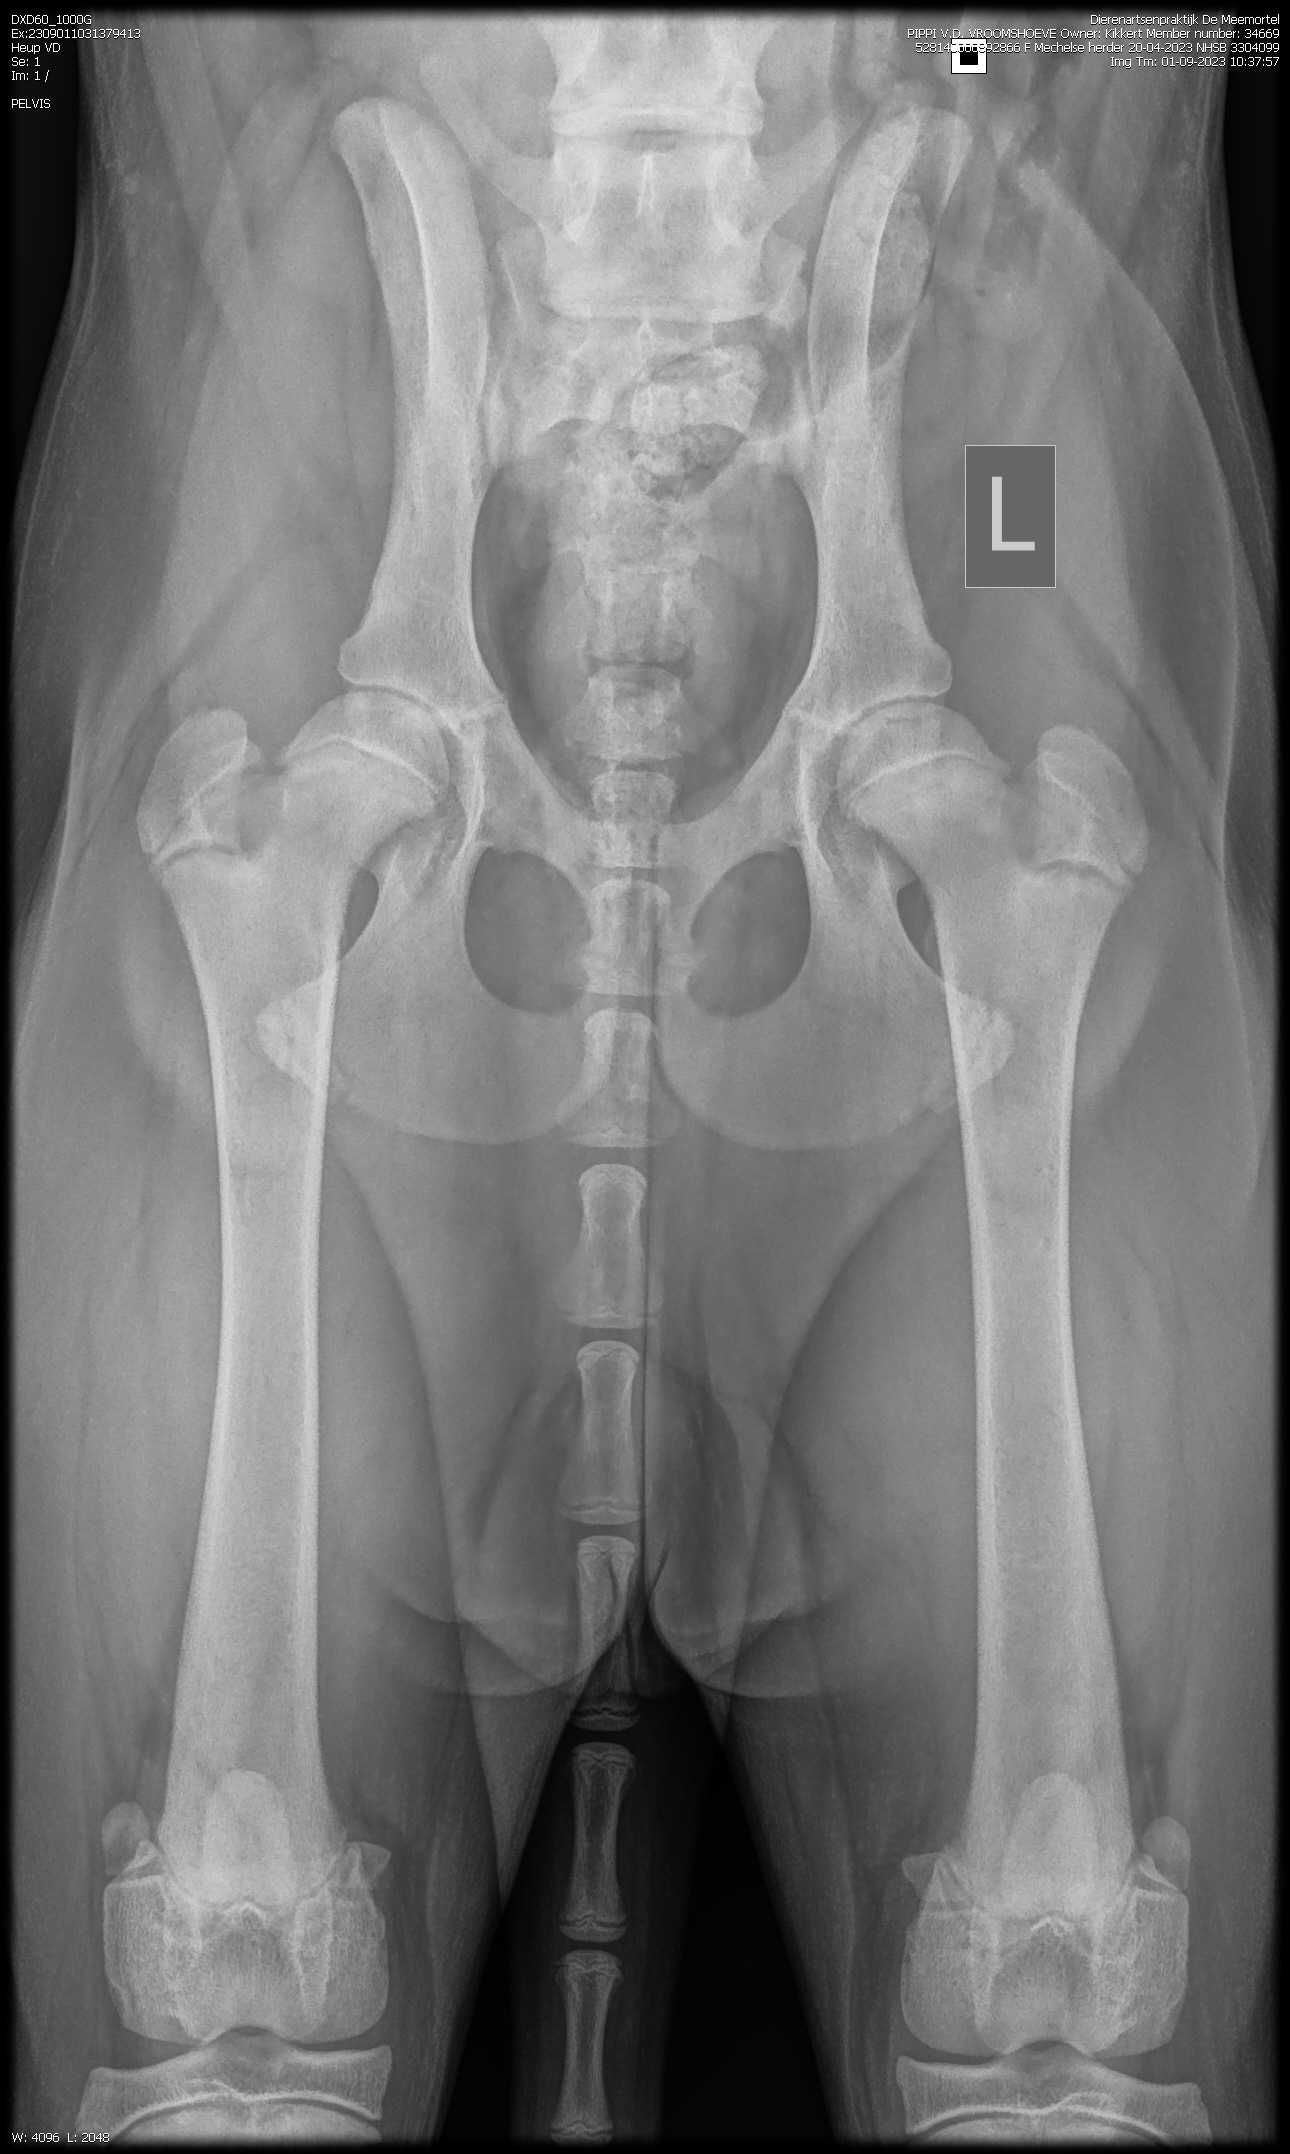

PennHip : Rechts DI 0.28 Links DI 0.16